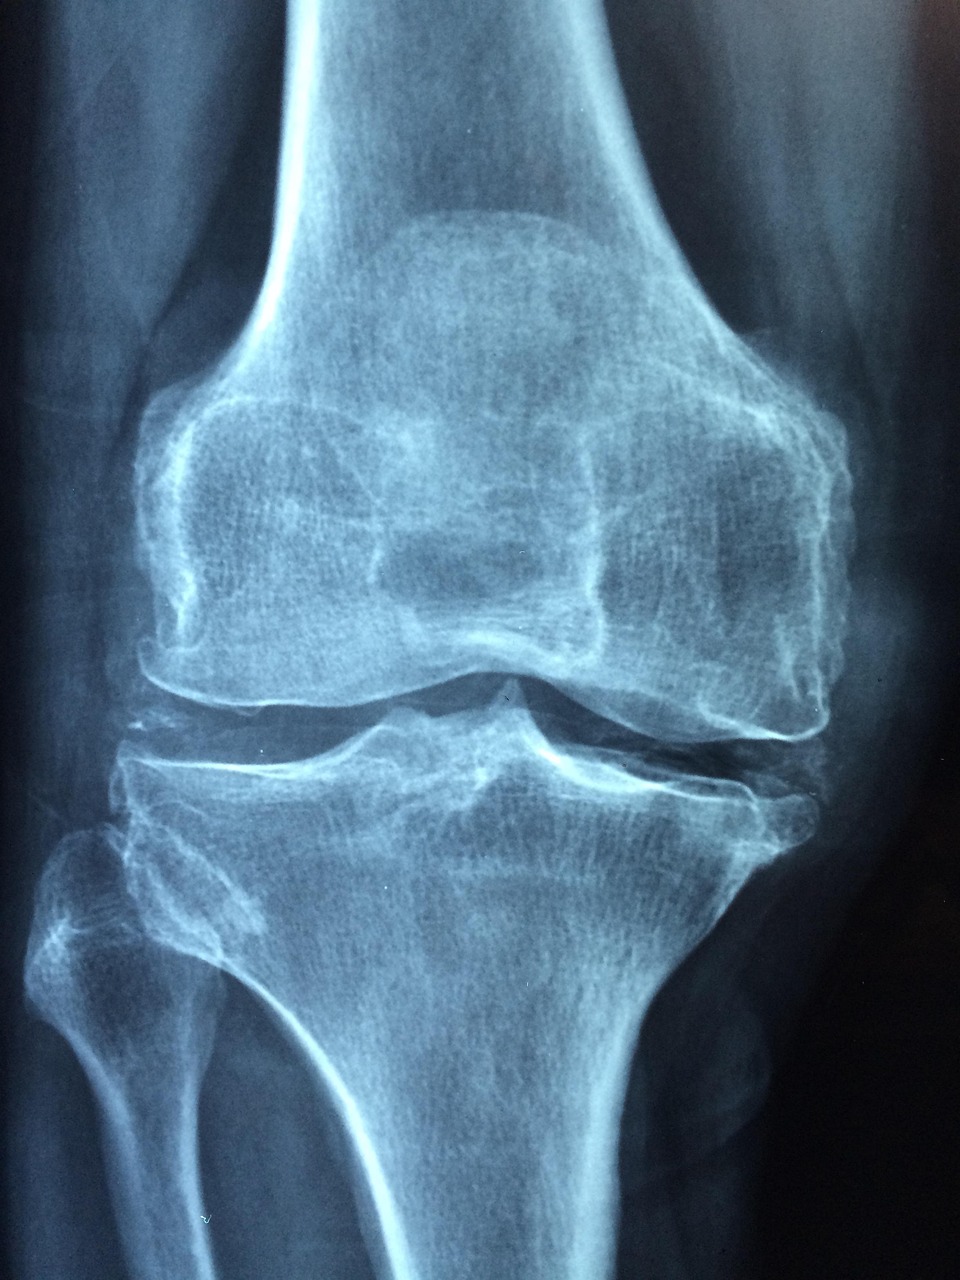

골다공증은 뼈가 약해지고 쉽게 부러질 위험이 높아지는 질환으로, 60대 이후에는 뼈 흡수 속도가 뼈 생성 속도보다 빨라져 골밀도가 급격히 감소합니다. 특히 60대 여성의 경우 폐경 이후 호르몬 변화로 위험이 더욱 높아지기에 60대 골다공증에 좋은 간식 및 식단 관리와 꾸준한 영양 보충이 예방의 핵심입니다.

골다공증은 왜 생길까?

• 뼈 밀도가 감소하며 약해지는 상태

• 폐경 이후 호르몬 감소로 특히 빠르게 진행

• 칼슘·비타민 D 부족, 운동 부족, 짜게 먹는 식습관 등도 위험 요인

• 넘어짐에 의한 골절 위험도가 높습니다.